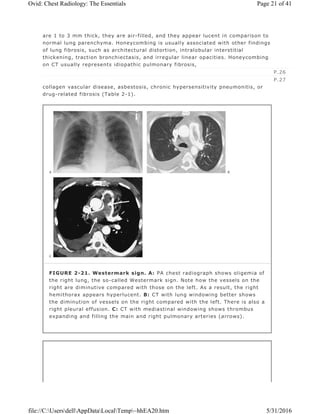

Westermark Sign

with pulmonary embolism (Fig. 2-21) (19).

FIGURE 2-21. Westermark sign. A: PA chest radiograph shows oligemia of

the right lung, the so-called Westermark sign. Note how the vessels on the

right are diminutive compared with those on the left. As a result, the right

hemithorax appears hyperlucent. B: CT with lung windowing better shows

the diminution of vessels on the right compared with the left. There is also a

right pleural effusion. C: CT with mediastinal windowing shows thrombus

expanding and filling the main and right pulmonary arteries (arrows).